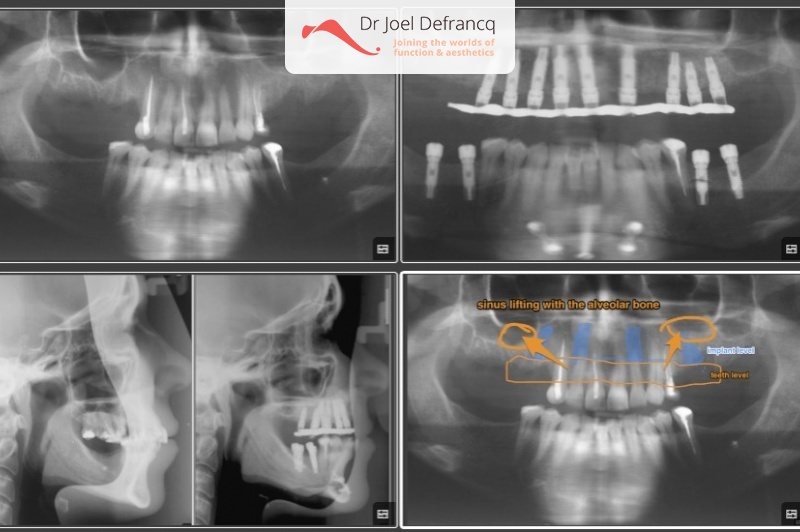

Josie: too much of the teeth showing, gummy smile, implants.

Dentale diagnose

- Klasse II divisie 1

Behandeling tandheelkundige implantaten

- Vaste tanden op implantaten (bovenkaak)